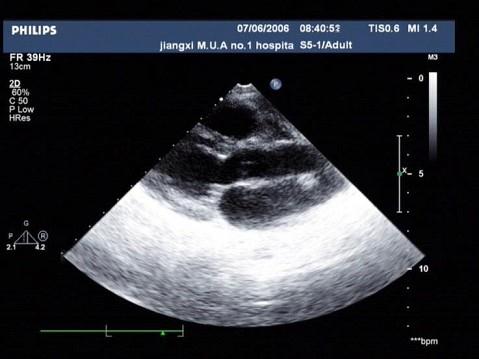

问题 图为小儿超声心动图,根据此切面可以看到哪些腔室结构?(?)

选项 A.左房、左室、主动脉、右室、右房 B.左房、左室、主动脉、右室、右室流出道 C.左房、左室、主动脉、右室 D.左房、左室、右室、右房 E.左房、左室、主动脉、左心耳、右室、右房、右室流出道

答案 B